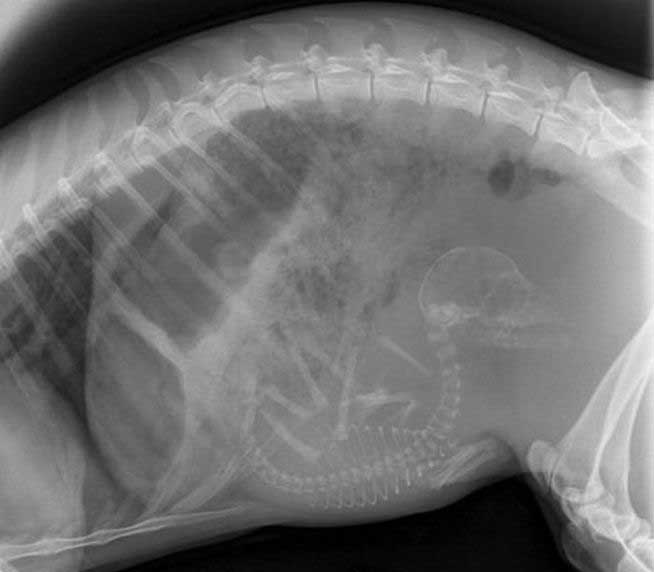

妊娠した様々な動物たちをレントゲン(X線)写真で見てみたギャラリー。サメ、ネズミ、犬、猫など。一度に複数の子供を出産する犬や猫などは特に怖い事に…。

9. トカゲ